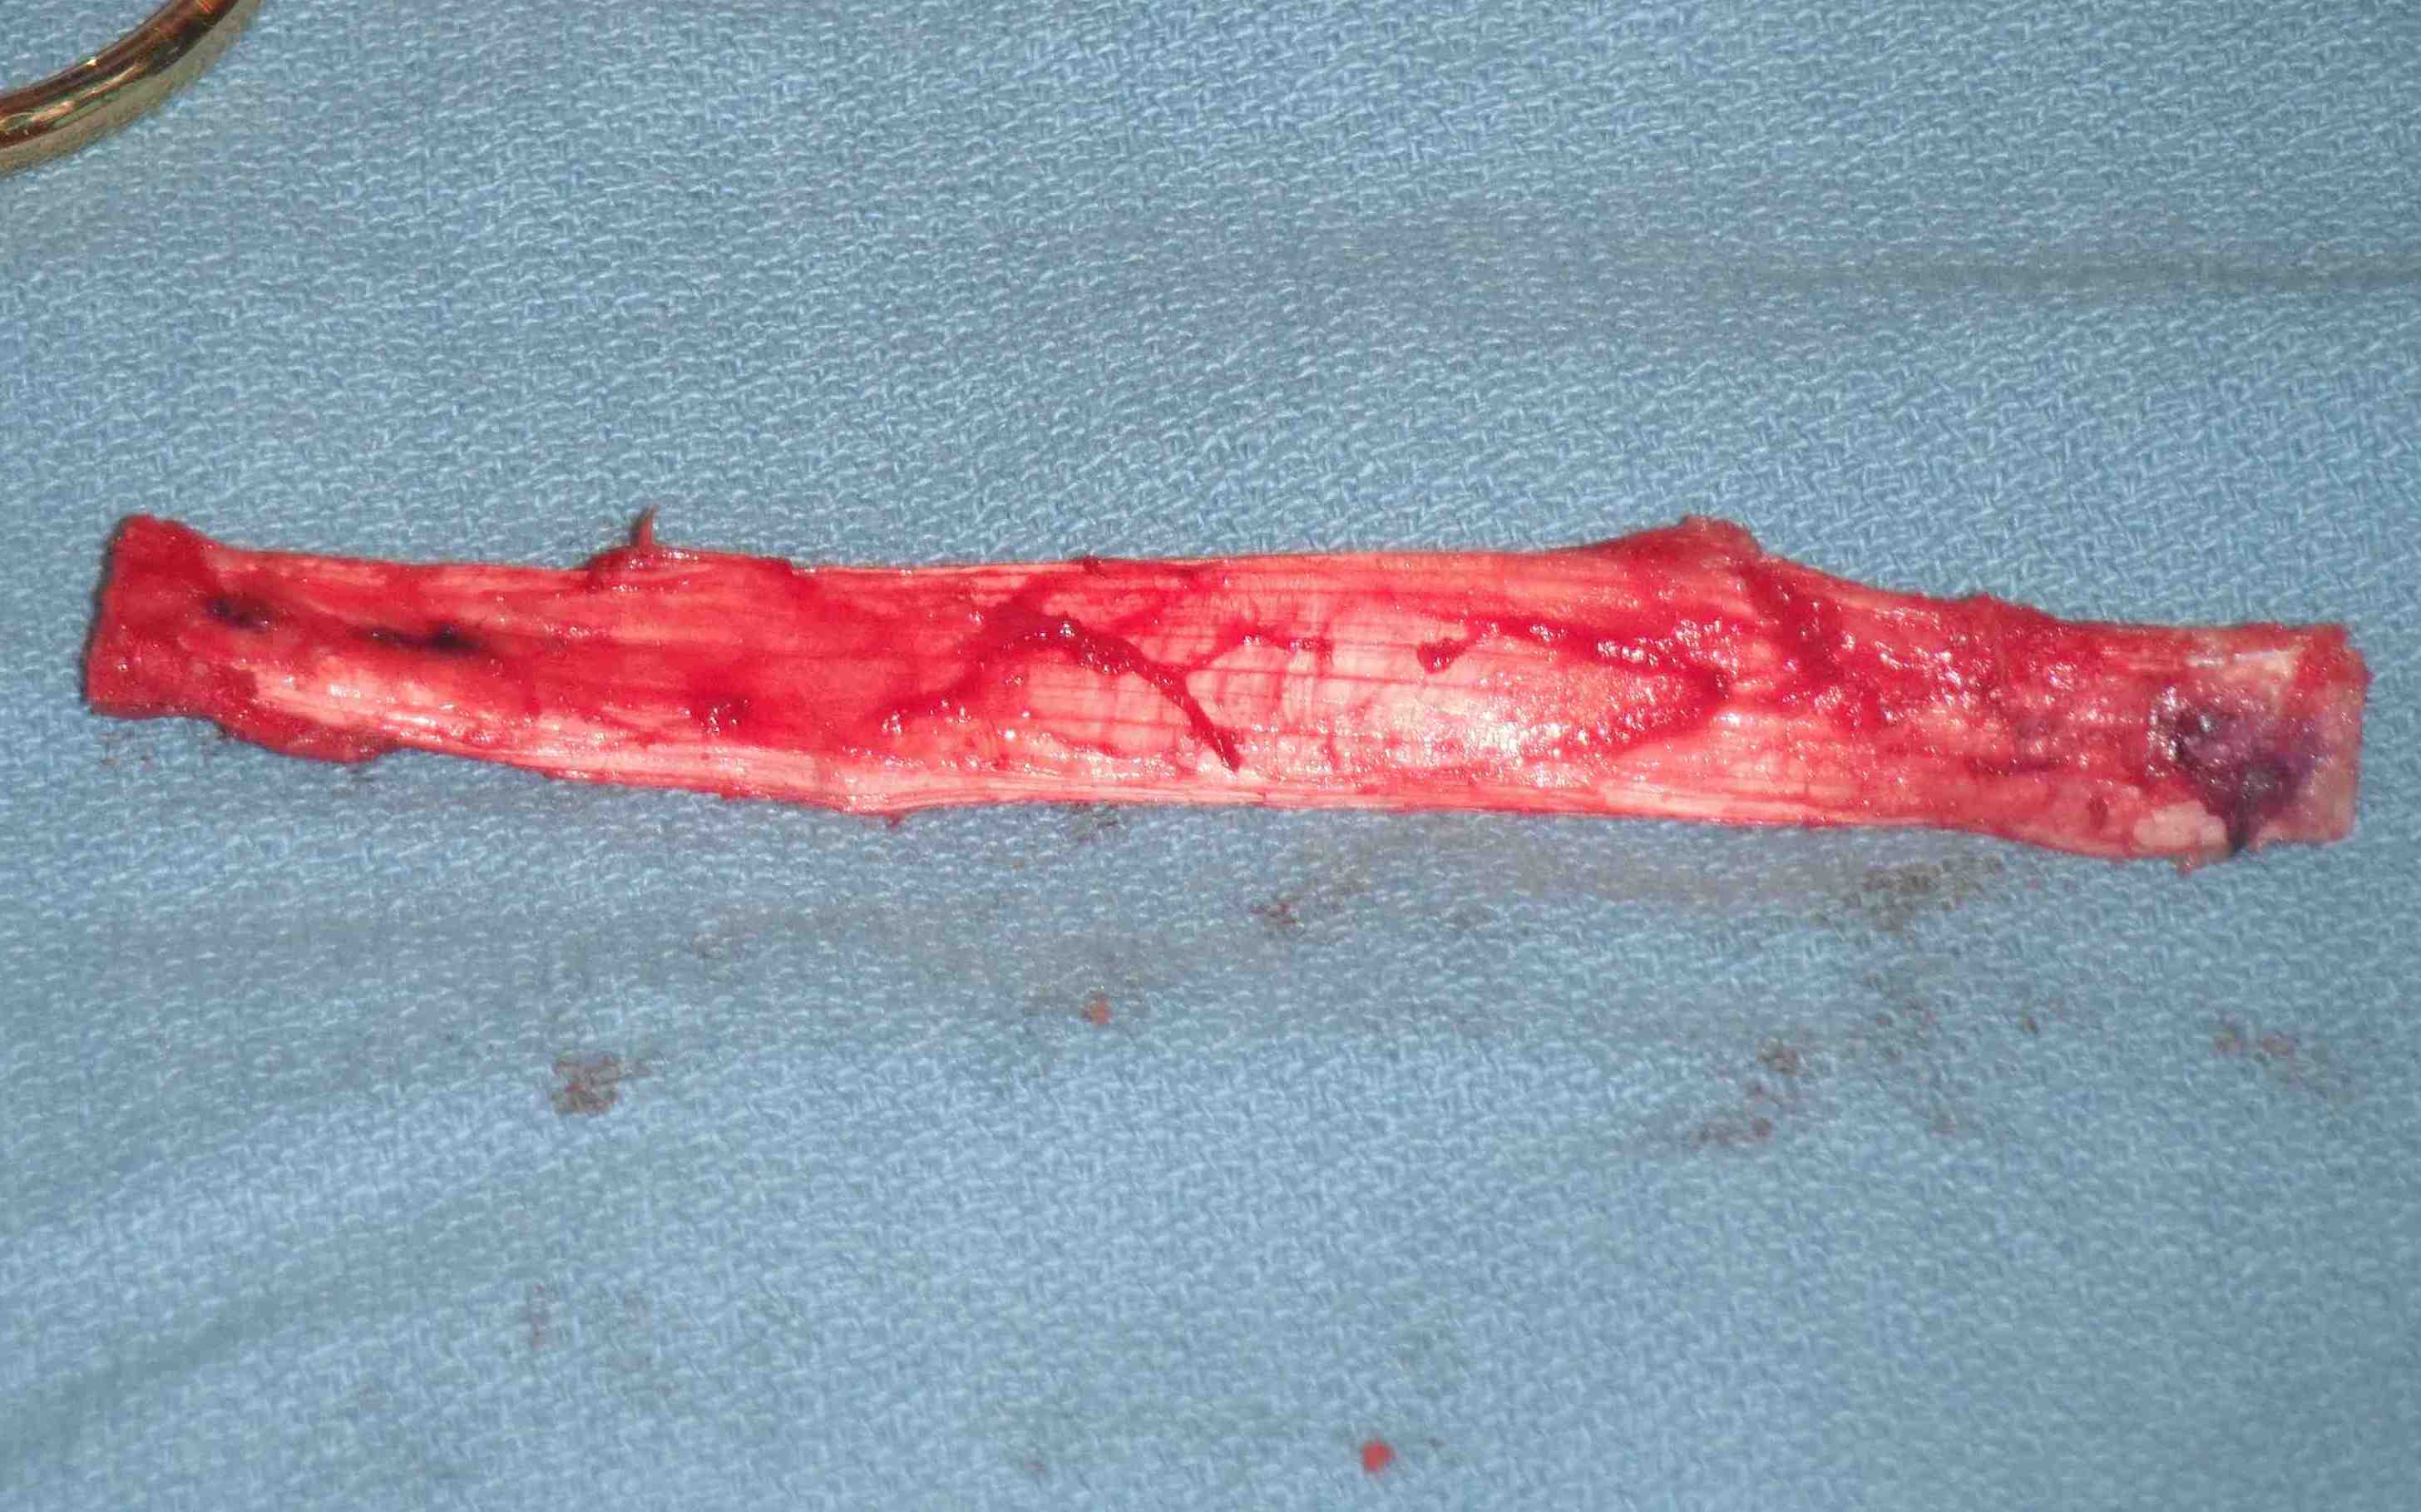

Graft preparation

Clean tendon of soft tissue

- decide which end will pass into femur

- usually the smaller piece

- nibble any sharp edges off especially on leading edge

- ensure whole graft will pass through 10 mm tube

- decide which end will be tibial or femoral

- mark femoral end with blue pen

- put 2 x 1 non absorbable sutures through drill holes

- probably don't need to tension BPTB